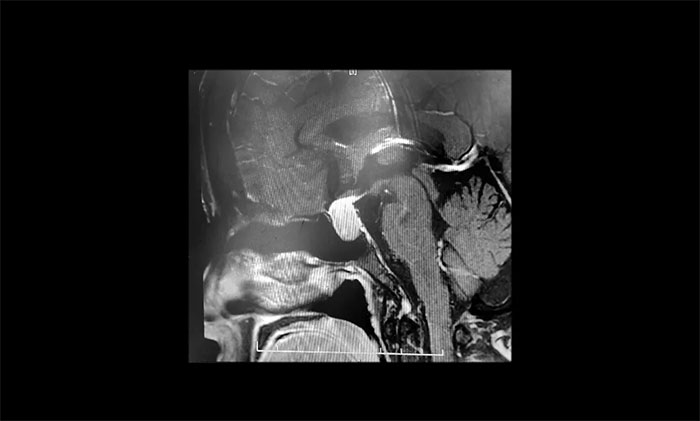

聽到腦袋里長了腫瘤,張阿姨一家人非常緊張,為謹(jǐn)慎起見,張阿姨在家人陪同下,特地到上海專業(yè)腦科醫(yī)院求醫(yī)復(fù)診。經(jīng)鞍區(qū)MRI平掃+增強(qiáng)檢查顯示:蝶鞍顯著擴(kuò)大,鞍區(qū)見T1、T2中等信號實(shí)性腫塊樣占位病變,垂體柄明顯縮短,病變總矢橫高徑約1.2*1.6*1.8cm,病變突破鞍膈,向鞍上生長,推移視交叉,視交叉受壓、上抬。

▲ 垂體大腺瘤超蝶鞍生長

神經(jīng)外科6B病區(qū)主任潘仁龍主任指出,患者垂體瘤較大,屬于垂體大腺瘤,患者的頭痛就是垂體瘤在作祟。并且腫瘤已經(jīng)壓迫視神經(jīng),手術(shù)指征明確,無明顯手術(shù)禁忌,應(yīng)及時手術(shù),否則往后發(fā)展患者視力也會受損。